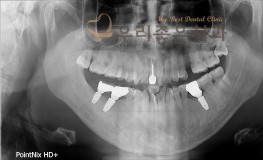

우리좋은치과 치아 상실로 인한 임플란트 보철 치료(강**2019.1.3~2019.5..

No.293

임플란트

2019-05-31

1535